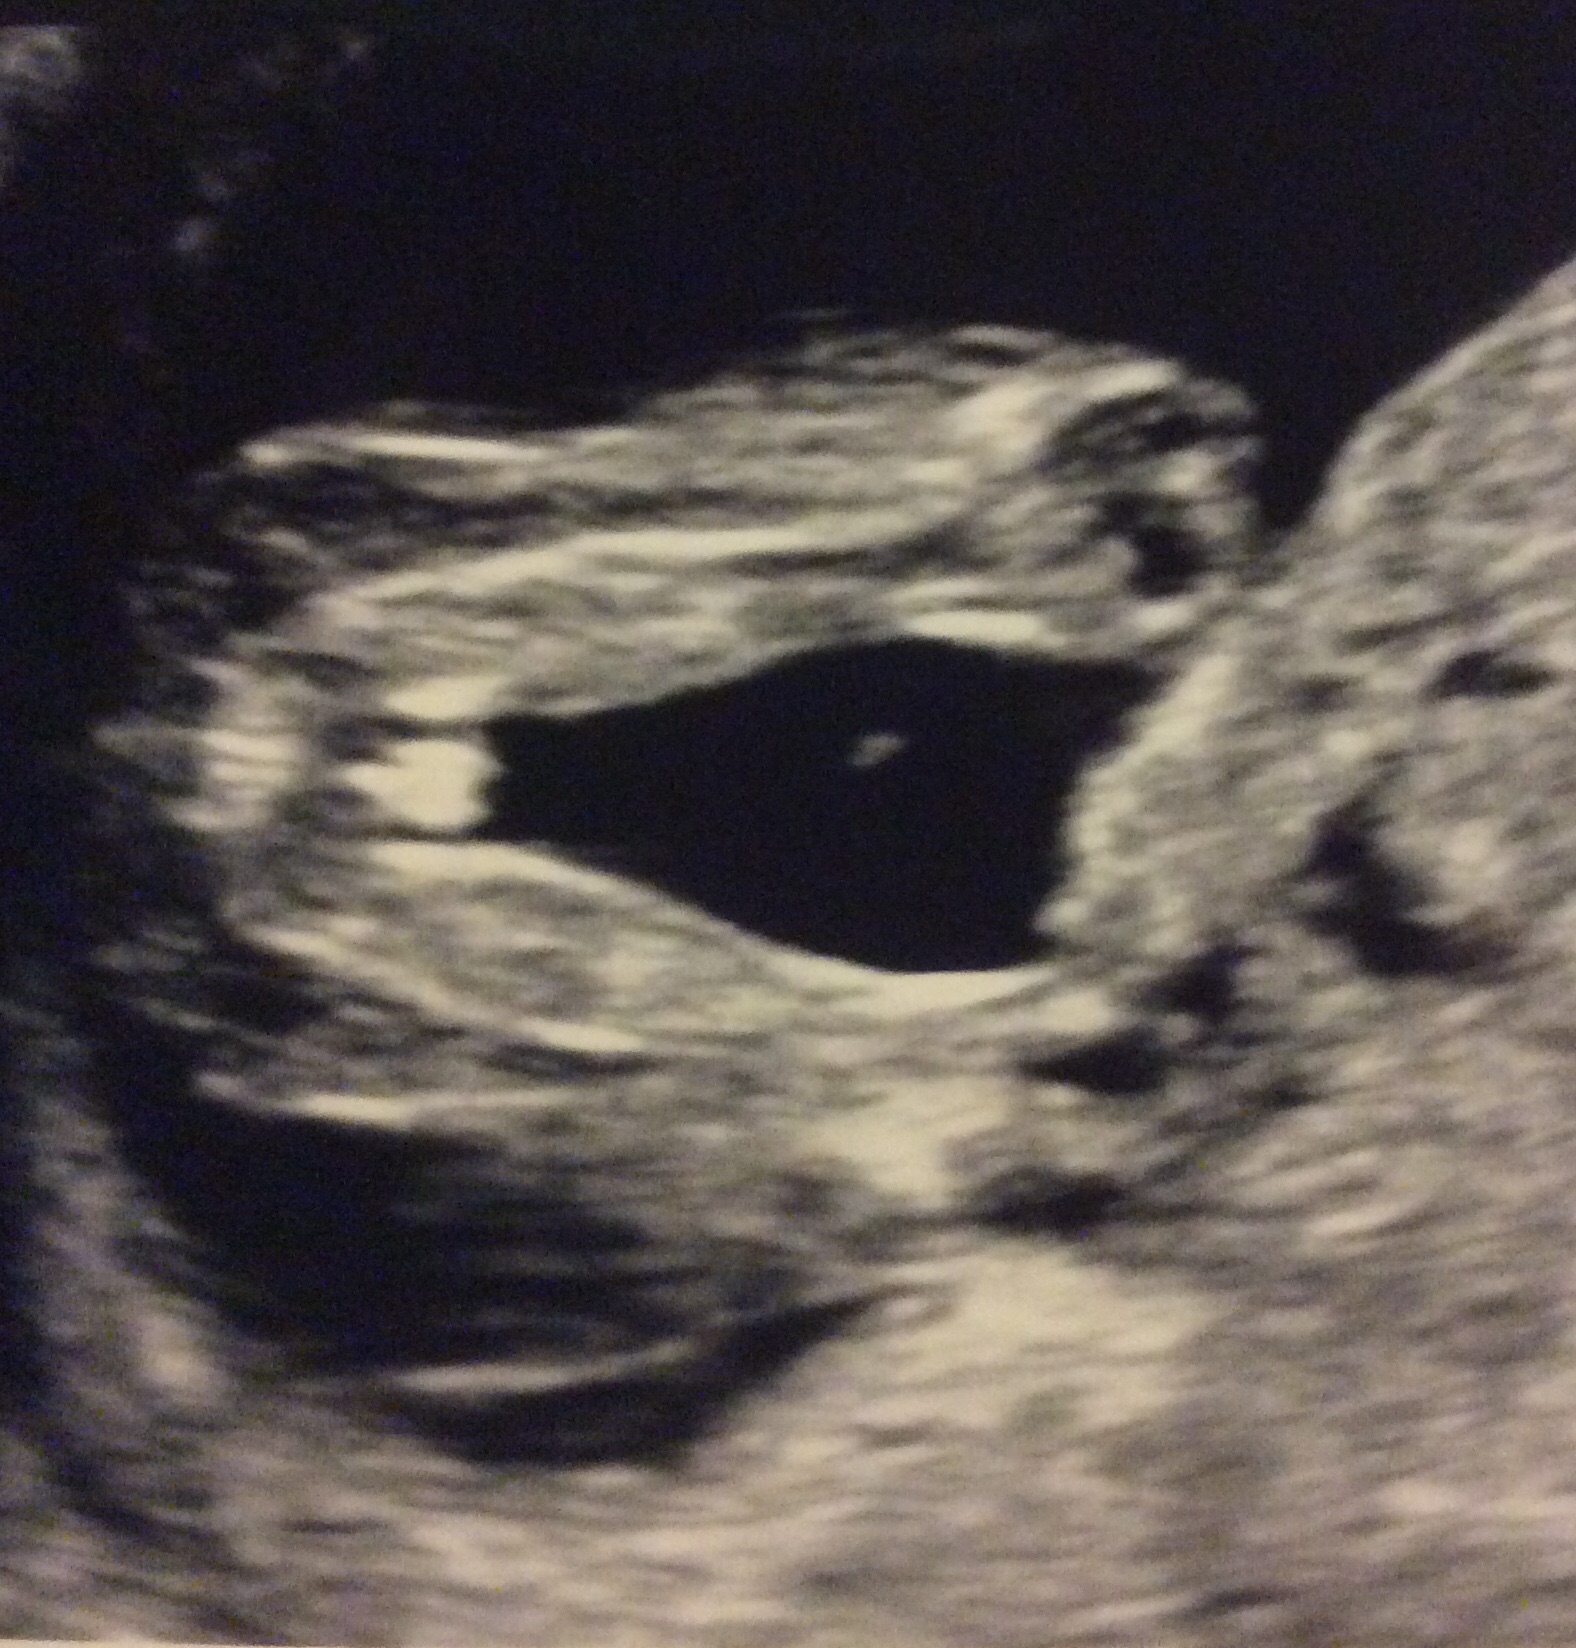

Don't know why this pic didn't go up but here it is. Attachment 24225

I like the last one better than the original one I colored for you. You've got a 3 line motion blur but still very discernible !

Last piccie is a definite girly hamburger. Go buy pink! x